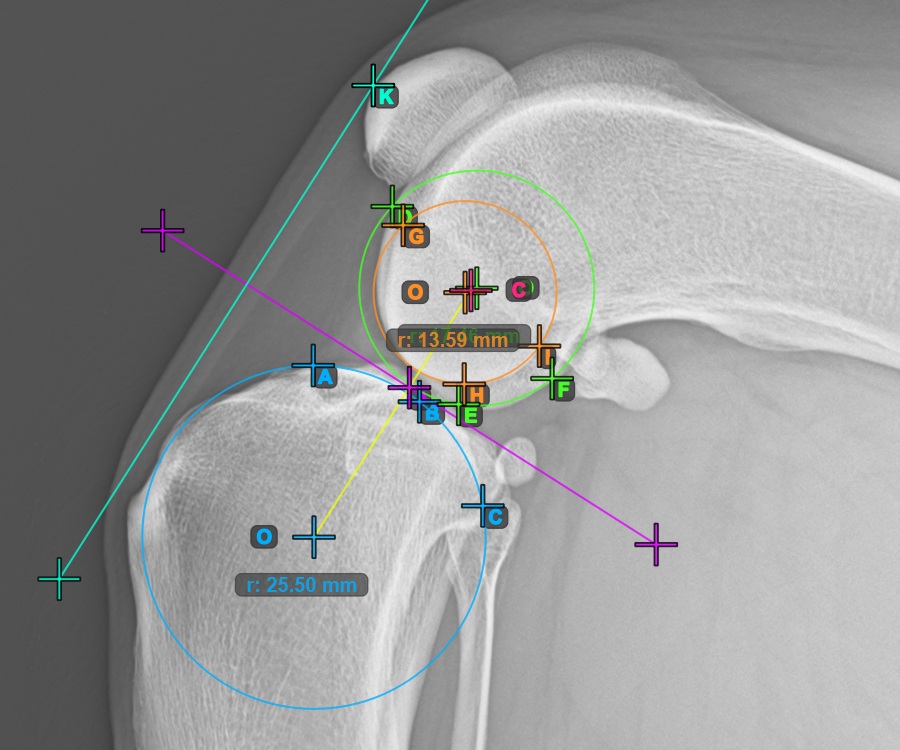

The image below represents a typical placement of the three points on the Condylus Medialis Tibialis.

![]()

Continue by marking the three points on the articular surface of the first Condylus Femoris.